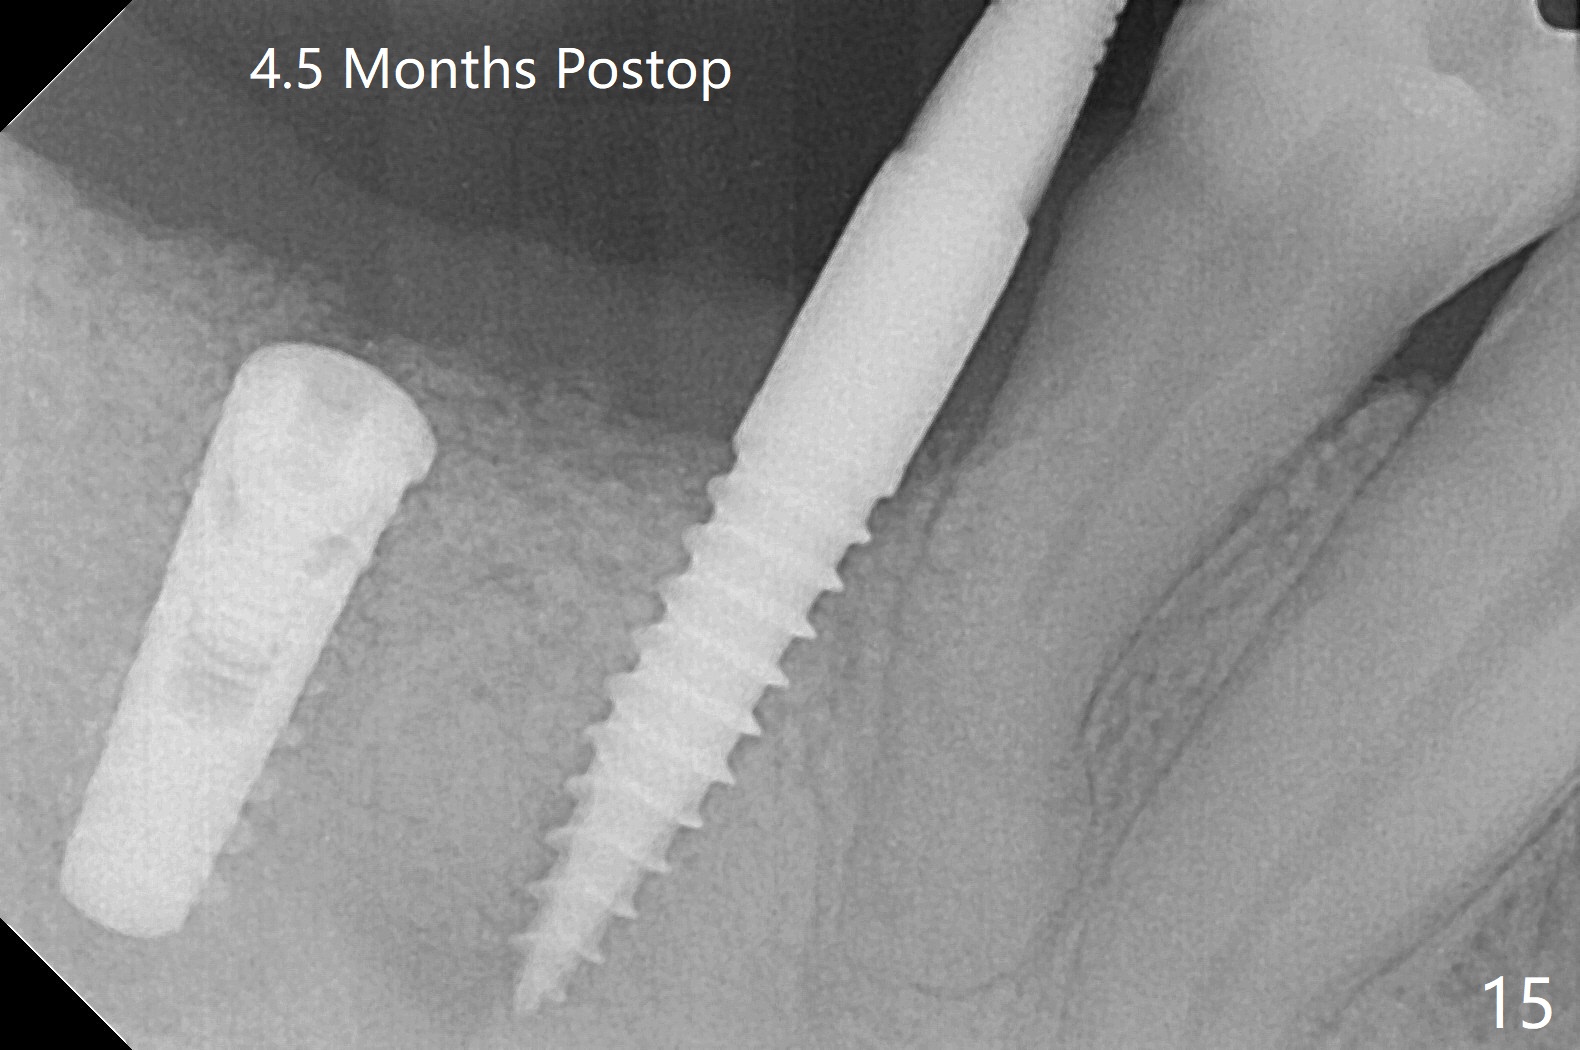

The implant at #30 was also buccally placed (Fig.6,7) and should be corrected in the same manner (Fig.7 green). Due to the bone being harder in the molar region, a smaller and shorter implant (4x11 mm vs. 5x13 mm) shifts slightly buccally while being placed (Fig.8,9). Since primary stability is lower (<20 Ncm vs. 35 Ncm associated with the implant #29), an abutment is not placed, which may be favorable to healing, but it is difficult to achieve primary closure. After bone graft (Fig.9 *) and 2 layers of PRF, Cytoplast is placed. Cytoplast appears to be exposed buccally (Fig.10 <) and occlusally (Fig.11 ^) asymptomatic 9 days postop. Exposure of Cytoplast is more distinct without sign of infection 15 days postop (Fig.12). The patient returns with chief complaint of "foul smell" 7 weeks postop (coronavirus lockdown). Although the Cytoplast exposes more (Fig.13 (* exposed; @ unexposed)), the underlying gingiva remains healthy (Fig.14). While the bone height decreases at #29, the bone density at #30 increases 4.5 months postop (Fig.15). The gingiva heals. The implant at #30 is uncovered 6 months postop. The lingual plate has to be removed for the uncover, while the coronal end of the buccal one is missing. No bone graft is added. When the 4.5x4 mm healing abutment is removed 6.5 months postop, the buccal plate looks concave at #30 (Fig.16' *). The buccal plate looks thin at #29 with a cotton roll placed buccally (Fig.16 R). The lingual plate at #29 is coronal to the buccal one (Fig.17). The buccal gingiva at #29 is quite long (Fig.18). The coronal buccal plate appears to be missing (Fig.19 >), which will be watched. A 4.5x7.5(4) mm cemented abutment is torqued (Fig.20).